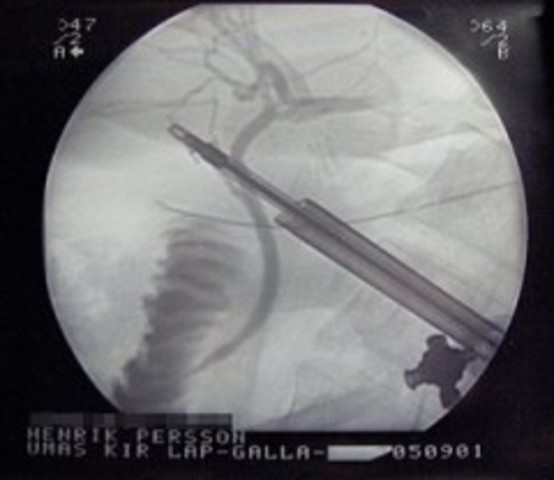

Por primera vez se utiliza un microscopio en una operación; actualmente en vez de microscopios, se utiliza la técnica “endoscopia” para realizar cualquier intervención quirúrgica demasiado pequeña para la vista humana. (http://timerime.com/es/evento/1182932/Endoscopia/)